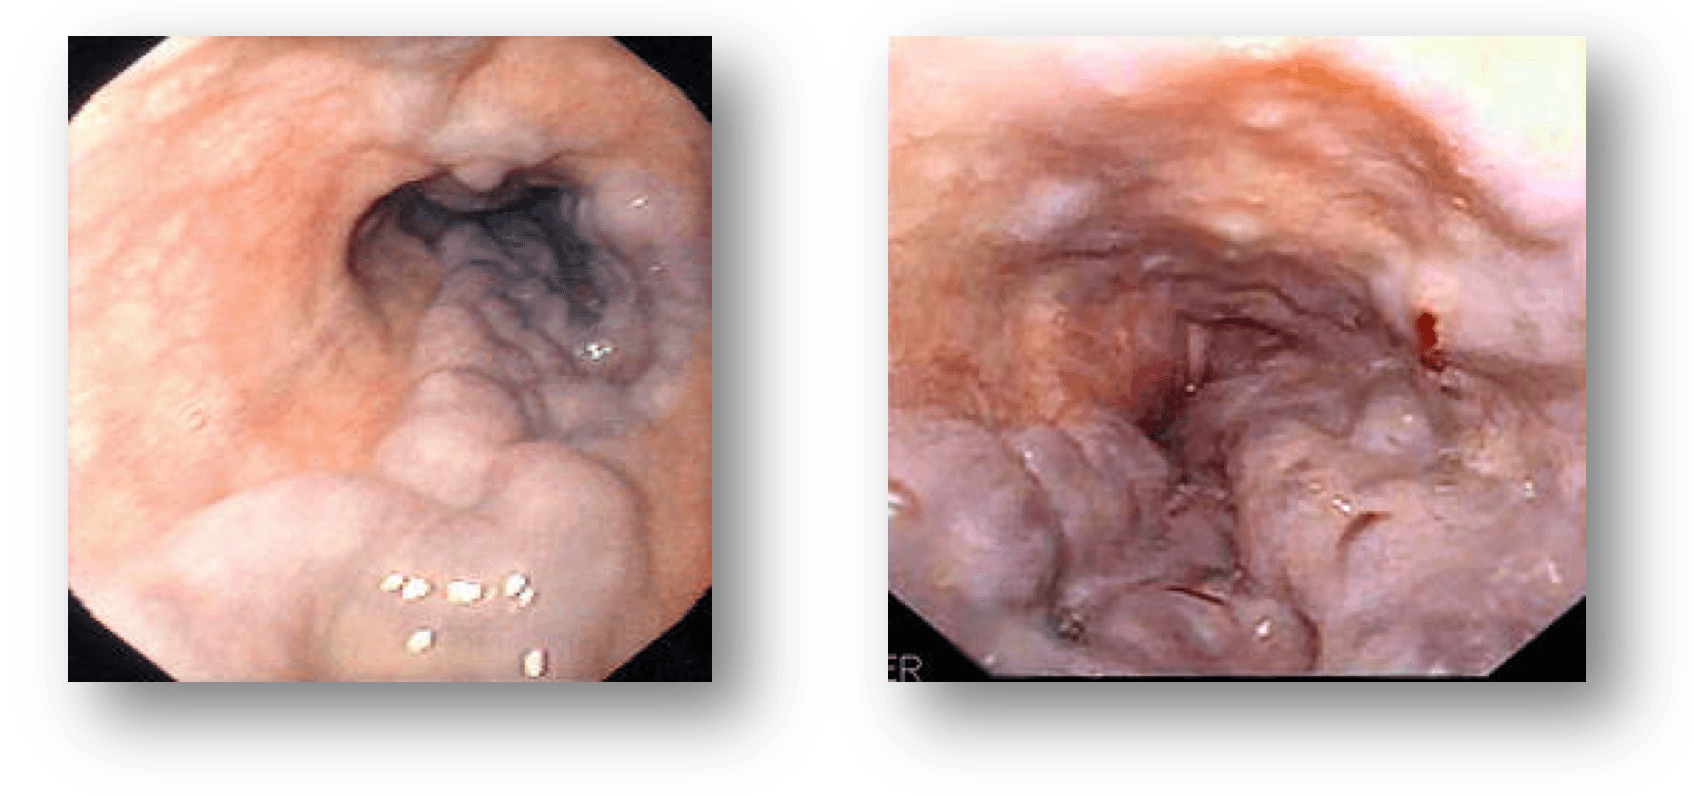

Dr; Me aconsejó mi médico que viniera porque tengo molestias de estómago y que me tendrán que hacer una Endoscopia oral, algo por la boca me dijo, que era necesario…¿Qué es eso? La Endoscopia oral di...

Dr; Me aconsejó mi médico que viniera porque tengo molestias de estómago y que me probablemente me harían una Endoscopia oral, por la boca...

PANENDOSCOPIA ORAL-. ¿Doctor, cómo tengo que venir para que me hagan la prueba? de la Endoscopia oral, Endoscopia Digestiva alta, Esofago gastro-duodenoscopia? Cierto de todas esas formas se le conoce al...